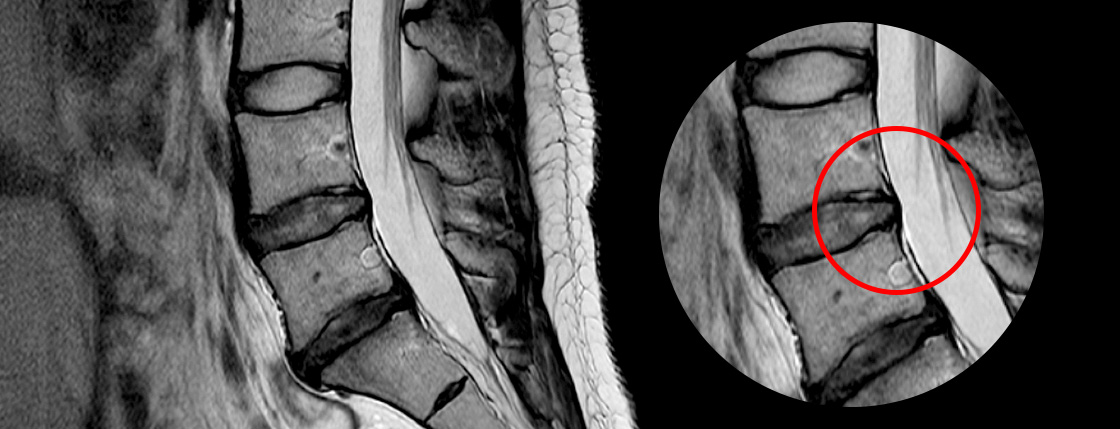

고주파수핵성형술은 디스크가 완전히 파열되지 않거나 아직 나이가 젊고 상태가 수술할 정도로 심각하지 않은 경우에 적용됩니다.

직경 2mm 이내의 가느다란 주사바늘을 문제가 생긴 디스크에 병변에 고주파에너지를 쏘아 척추신경을 압박하는

디스크내의 분자를 분해하고 녹인 후 수축 응고시키는 치료 방법입니다.